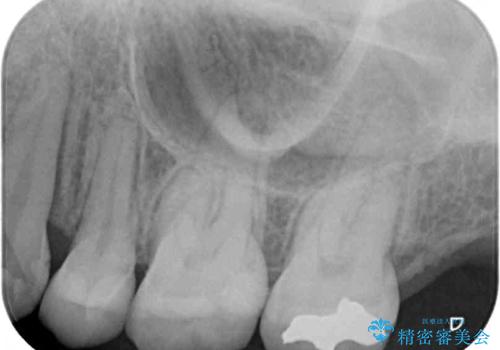

- 他院で抜歯矯正を終えた後、銀色の目立つ奥歯を白くしたいとのことで来院された患者様です。

既にセラミッククラウンが装着されている歯もありますが、不自然な色合いや黒い縁も気になるので、一斉に補綴治療をして統一感を持たせることとしました。

矯正治療を終えたばかりなので、仮歯やセラミッククラウンに置き換えている間に保定がうまくいかなくなる可能性があるため、下顎前歯の舌側を事前にワイヤーで保定しておくこととしました。